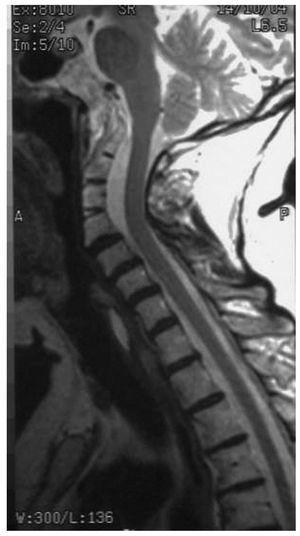

Figura 2. Resonancia magnética que muestra hipoplasia y fusión parcial de los cuerpos vertebrales C2, C3 y C4.

Con la sospecha de patología atlantoaxoidea se solicita radiografía cervical, apreciándose en la proyección lateral (fig. 1) fusión de las articulaciones interapofisarias posteriores y bloque C2-C4, con lo que se establece la sospecha diagnóstica de síndrome de Klippel-Feil. Se realiza tomografía axial computarizada (TAC), donde se describe fusión occipitoatlantoidea, fusión de los cuerpos vertebrales y de los elementos posteriores de C2, C3 y C4, atrofia de los discos intervertebrales y disminución del diámetro anteroposterior de los cuerpos vertebrales. Ante los hallazgos de la TAC se recomienda realizar una resonancia magnética (RM) para estudiar el canal medular. En la RM (fig. 2) se observa acentuación de la lordosis en los niveles C2 - C3 - C4 asociada a fusión parcial de dichos cuerpos vertebrales con hipoplasia relativa de los mismos; se excluyen compromisos mecánicos extrínsecos sobre la unión bulbomedular o cordón medular. La RM confirma la existencia de síndrome de Klippel-Feil tipo 2 sin compromiso neurológico.